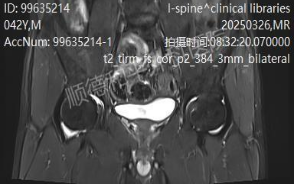

经过详细的门诊查体、问诊,及专业的阅片,患者被诊断为“腰椎滑脱(L5及以上椎体向前移位约6mm)、腰椎间盘突出伴神经根病”,随后被精准收治于骨科二区(脊柱外科)。

骨科二区的医疗团队在收治患者后,进行了更详细的摄片检查,并迅速对其病情进行了全面评估和深入讨论。考虑到患者的症状严重影响日常生活,且保守治疗效果不佳,手术治疗成为解决问题的关键。